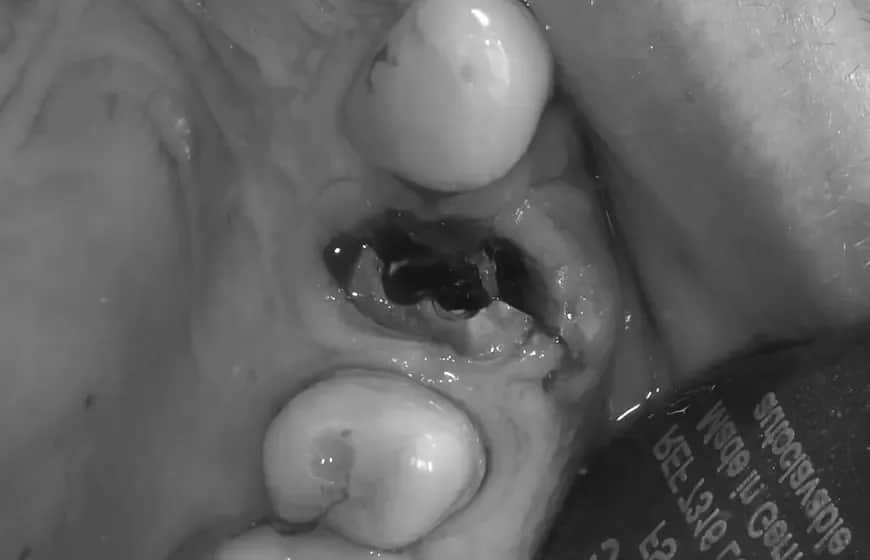

Masz torbiel na dziąśle? Dowiedz się, jak wygląda, jakie daje objawy i czy jest groźna. Poznaj skuteczne metody leczenia i diagnozy. Sprawdź!